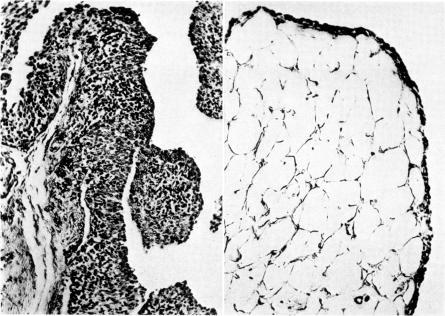

Eight-week-old pigs fed a protein-rich diet developed an abnormal intestinal microbial flora within 1 week. The main feature was a significant increase in the number of atypical , type A. In the first week after the change of diet, the pigs showed disturbances of movement and swollen peripheral joints. The ESR was concomitantly elevated and later on hypergammaglobulinaemia with increased antibody titres to antigens were noted. Joint deformities were observed after some months. The joint lesions consisted of synovitis with a cell-rich exudate. The lesions of the synovial tissue were characterized by proliferation of the synovial lining cells with villous hypertrophy and highly vascularized granulation tissue containing accumulations of lymphoid cells. Pannus formation and erosion of joint cartilage were seen in some animals. Bacteriological examination, including search for mycoplasmas, was negative. Subcutaneous nodules of rheumatoid nature were also found. Signs of proliferative glomerulonephritis were demonstrated in most of the animals. Different pathogenic aspects are discussed with regard to the direct influence of antigens on the joint tissues, circulating antigen–antibody complexes and cell-bound antibodies. As the same abnormal intestinal flora and immunological reaction to intestinal have been found in human rheumatoid disease, this diet-induced pig arthritis of remarkably similar clinical and histological characteristics is of special interest.

八周龄的猪喂食富含蛋白质的日粮后,在1周内肠道微生物群就出现异常。主要特征是A型非典型菌数量显著增加。在日粮改变后的第一周,猪出现运动障碍和外周关节肿胀。同时血沉升高,随后出现高球蛋白血症,抗体对抗原的滴度增加。几个月后观察到关节畸形。关节病变包括伴有富含细胞渗出液的滑膜炎。滑膜组织病变的特征是滑膜衬里细胞增殖、绒毛肥大以及含有淋巴细胞聚集的高度血管化肉芽组织。在一些动物中可见血管翳形成和关节软骨侵蚀。包括支原体检测在内的细菌学检查均为阴性。还发现了类风湿性质的皮下结节。大多数动物显示出增殖性肾小球肾炎的迹象。就抗原对关节组织的直接影响、循环抗原 - 抗体复合物和细胞结合抗体等方面讨论了不同的致病因素。由于在人类类风湿疾病中也发现了相同的异常肠道菌群和对肠道的免疫反应,这种饮食诱导的猪关节炎在临床和组织学特征上与人类非常相似,具有特殊的研究意义。